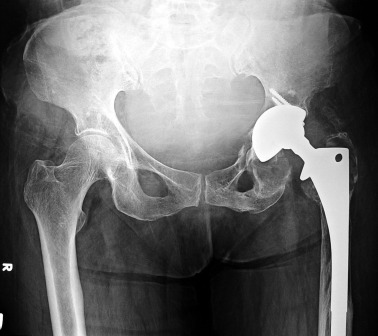

Aiming to clarify the relationship of the mass to the prosthesis, a pelvic MRI examination was scheduled (Fig. 2 ). The lesion was hypointense in T1 and hyperintense in T2 weighted images. There were no solid components within the mass as well as a contrast enhancement. The heterogeneous material within the lesion appeared hypointense on both sequences. It had smooth contours and a thin, and hypointense wall with equal thickness throughout its circumference. There was significant displacement of the bladder and the uterus, and the mass caused significant separation between the bladder and the rectum. Hydronephrosis was due to compression and displacement of the ureteric insertion. The key finding of the presence of a focal continuity between the medial acetabular wall and the lesion, identified the hip as the origin of the lesion, leading to the diagnosis of a pseudotumor.

Coronal T2 weighted MRI. The mass is heterogeneous in nature, T2 hyperintense ...

Coronal T2 weighted MRI. The mass is heterogeneous in nature, T2 hyperintense and compresses the left ureteric orifice causing ureteral dilation.